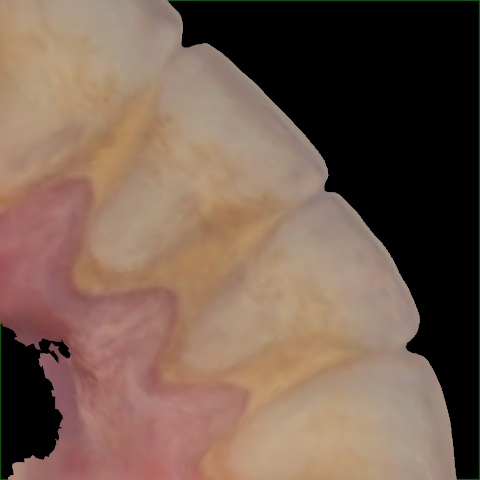

Annotated as "Good"

Original Image Rendering Image